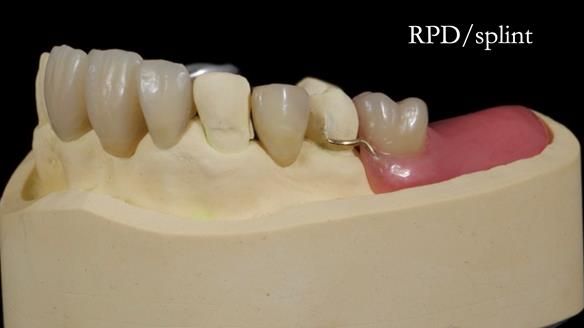

This edition features the case of Edgar, who sought help for a poorly fitting, acrylic-based partial denture that rocked, affected his speech, and caused discomfort. After considering various treatment options, including dental implants, Edgar opted for a metal-based removable partial denture, designed by myself with input from my technician, Rowan Garstang.

Treatment Process: I provided the clinical work while Rowan Garstang delivered the technical aspects. The treatment required fifteen visits to fit and review Edgar.